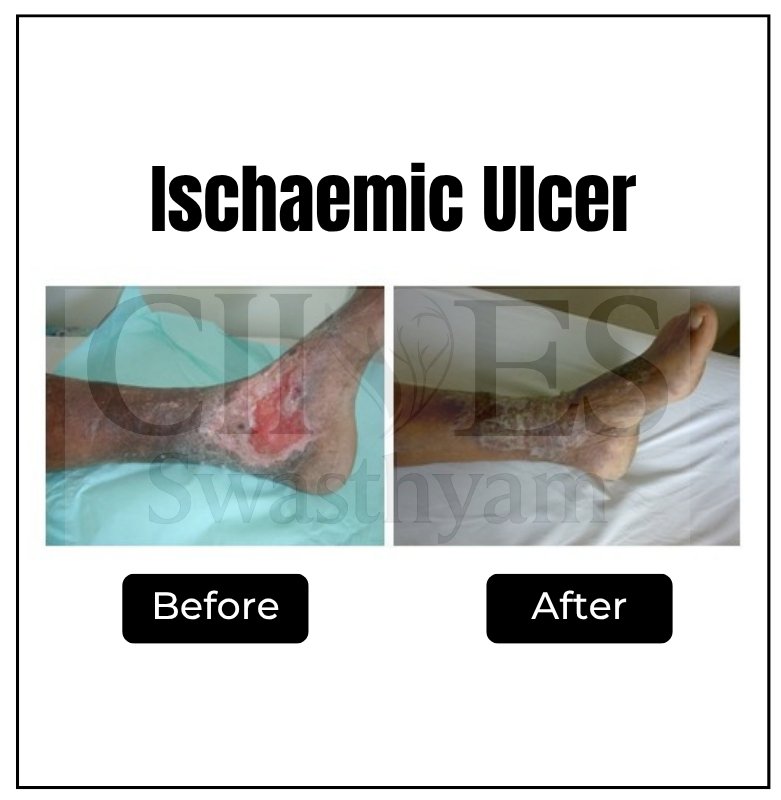

Poor circulation and high blood sugar create an environment prone to infections and impaired healing. If left untreated, these injuries can turn into non-healing ulcers and, in severe cases, lead to gangrene (black foot), where tissue dies and amputation may be necessary.

Discover how minimally invasive treatments help relieve pain and improve the appearance of legs.